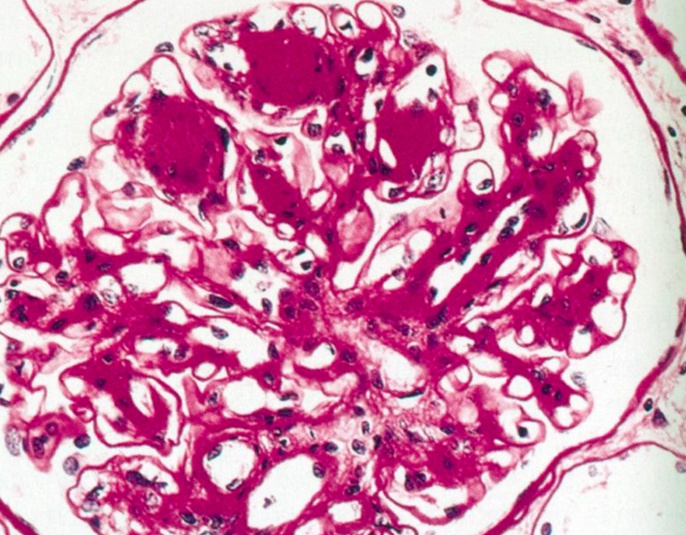

Diffuse:

Nodular:

Kimmelstiel-Wilson Nodules

_..